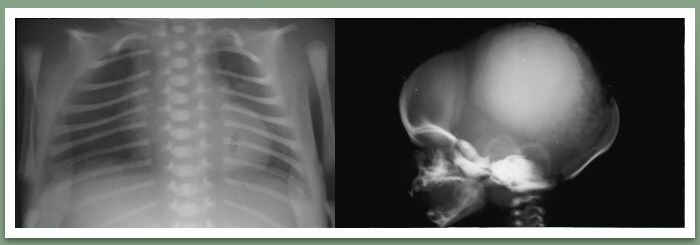

The Skeletal Dysplasia Group was founded in 1979 with the aim of promoting teaching and research into the rare developmental disorders of skeletal growth (osteochondrodystrophies). Members include professionals from all relevant branches of medicine and basic sciences including geneticists, radiologists, orthopaedic surgeons, paediatricians, genetic nurses, endocrinologists and rheumatologists.

The conditions we are starting with (in children and adults) are osteogenesis imperfecta and fibrous dysplasia. We are working with the Brittle Bone Society and Fibrous Dysplasia Support Society UK to help develop the database and ethics. We aim to start recruiting in April 2014 and have started drafting the protocol and data collection templates, which we would request your input into.